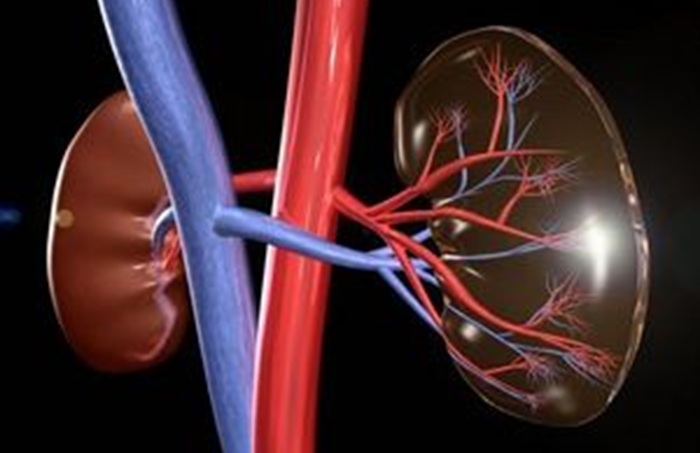

Метод ультразвуковой диагностики, дающий оценку состояния сосудов почек, называют дуплексное сканирование. Боль в пояснице, нарушение мочеиспускания, колики и другие симптомы характерны для заболеваний, которые могут развиться при нарушении кровотока в этом органе. В диагностике сосудистых болезней сканирование артерий почек занимает центральное место, так как оно объединяет сразу два обследования: допплерографию сосудов и прилегающих тканей. Кроме того, дифференциальная диагностика проводится врачом для выявления подозрений на несколько заболеваний. Процедура полностью безопасная и безболезненная.

Процедура сканирование сосудов проводится врачом с целью оценивания состояния: кровотока вен, питающих почки, почечных артерий. Методика основывается на применении эффекта Доплера. Ультразвуковые лучи отражаются от элементов движущийся крови и возвращаются в прибор обратно. Анализатор в приборе сканирует данные, после чего они отображаются на экране монитора. Таким образом датчик преобразует сканируемые сигналы, по выводимым данным строится график, а также двухмерное изображение сосуда. Кроме того, производится расчёт значений и цветное картирование.